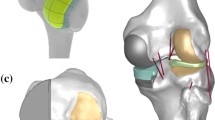

The patient-specific TKA is designed using an existing three-dimensional (3D) knee joint model [19, 20]. A patient’s bone is fundamentally used for the patient-specific geometry in the femoral component. The three patient-specific J-curves and the medial and lateral condyles from the patients’ normal articular anatomy are developed using computer-aided design (CAD) software in this study [17, 21,22,23,24,25]. A sagittal plane is introduced in the condyles, in which the anatomy of the articulating surfaces is extracted from the curves. Generally, the femur of a patient in the coronal plane provides asymmetric lateral and medial condyles that are defined as the coronal offset. The aforementioned patient-specific differences are considered in the patient-specific femoral component design (Fig. 1). The coronal offset is defined as the difference in height between the medial and lateral femoral condyles in the coronal plane [17, 26]. It typically supports an asymmetric extension gap between the tibial articular surface and the posterior femoral condyles. The lateral posterior condyle is shorter than the medial condyle and leads to an asymmetric flexion gap [17, 26]. The aforementioned femoral J-curves are matched with patient-specific tibial inserts, and their perimeters correspond to a tibial plateau that restores the distal medial-lateral offset of a patient’s femoral condyles. This is achieved by the height of the patient-specific tibial insert and reflects the condylar offset to maintain normal mechanical axis alignment. The articular geometry in a patient-specific tibial insert used in a previous study was derived from the femoral component [13, 26, 27].

The ratio of the curvature radius for the tibial insert to the curvature radius for the femoral component is investigated for conformity in the coronal and sagittal planes. A tibial insert with a conforming design of conventional CR TKA conformity (Genesis II) and a medial pivot tibial insert with medial pivot conformity (Evolution) are developed by applying the curvature radius ratio in the coronal and sagittal planes to the patient-specific femoral component (Fig. 2). An anatomy tibial insert is developed using a patient’s tibial curvature and is similar to the femoral component. The bone coverage exceeded 95% in the patient-specific TKA, irrespective of differences in the insert design (Fig. 2). All of the femoral component designs in the patient-specific TKA are identical.

Furthermore, MPS-TKA with medial pivot conformity exhibits better wear performance. Based on in vivo and in vitro studies of the physiological movements during flexion, the medial femoral condyle does not significantly translate in the AP direction while the lateral condyle moves significantly backward [42,43,44]. Thus, the medial pivot geometry exhibits a highly conformed “ball-in-socket” design to reproduce the medial pivot motion on the medial side. Several studies have indicated that during flexion (termed as a “medial pivot”), a normal knee provides minimal movement of the medial femoral condyle and a posterior translation of the lateral femoral condyle [45,46,47,48]. The implant is introduced to provide the aforementioned characteristics. The medial side exhibits a design with an identical curvature radius on the coronal and sagittal planes to recreate a sphere. The lateral side is smaller than the medial with a cylindrical configuration, and it can stabilize the knee and control rotation. Additionally, the PE asymmetrical insert exhibits a high medial side congruence and a minor lateral congruence. The aforementioned innovations allow for lateral-side posterior sliding and rolling, while the medial side functions as a pivot during knee flexion and guarantees AP stability. The medial pivot design provides better stability and range of motion, less wear stress on the tibial surface, and longer PE survival. These phenomena are reduced by a medial pivot design with better stability and important PE wear reduction [49,50,51,52,53,54,55]. Therefore, as previously mentioned, MPS-TKA exhibits better wear performance than CPS-TKA, BPS-TKA, and conventional TKA.